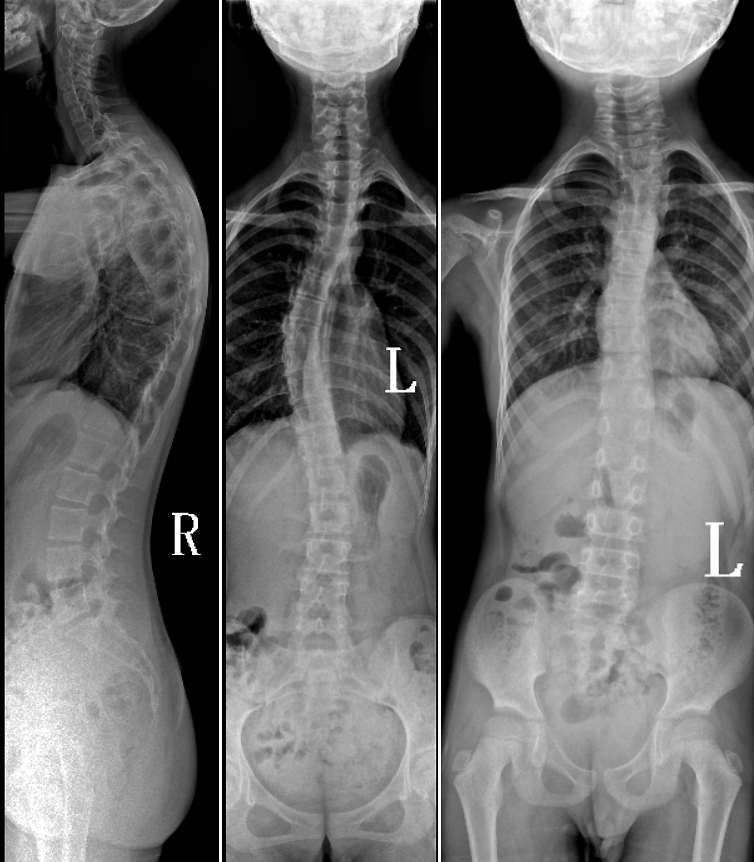

DR是臨床骨科的重要檢查手段之一。在骨科檢查中,脊柱矯形、長(zhǎng)骨骨折、腰椎退行性病變等,需要采集脊柱、下肢全景圖像,輔助醫(yī)生臨床診斷,從而制定科學(xué)的治療方案,普愛(ài)醫(yī)療的大視野平板動(dòng)態(tài)DR就像是一座橋梁,連接起現(xiàn)代醫(yī)療技術(shù)與當(dāng)?shù)厝嗣竦尼t(yī)療需求。

普愛(ài)醫(yī)療自主研發(fā)的大視野平板動(dòng)態(tài),采用17"*34"的有效視野,一次曝光即可得到全脊柱或全下肢影像。相較于多張攝影再軟件拼接的DR設(shè)備,PLX8600解決了拼接圖像存在密度不均勻,拼接處圖像配準(zhǔn)和放大效應(yīng)等問(wèn)題,給臨床帶來(lái)了真正的大視野影像解決方案。